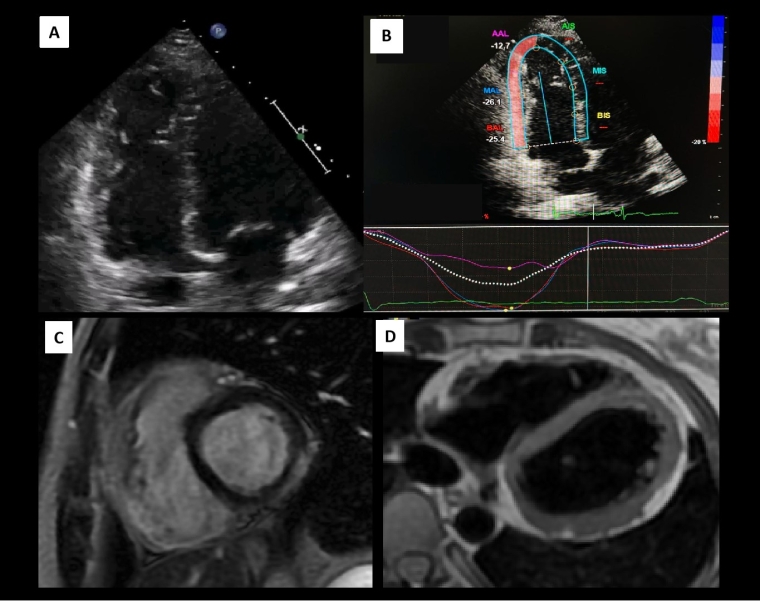

Generally, athletes with MVP have an excellent long-term prognosis. However, although uncommon, a malignant phenotype associated with life-threatening ventricular arrhythmias (VA) [31,32] has been identified. Recent studies using TTE and CMR have found morphological characteristics associated with this phenotype, regardless of MR severity or LV remodelling. These include bileaflet prolapse, mitral annular disjunction and superior displacement of papillary muscles (PM) [31,32].

It is believed that these alterations generate mechanical tension in the inferolateral myocardial wall and in the PM, which can cause mechanical dispersion (double peak strain in STE by TTE) and replacement myocardial fibrosis (demonstrated by LGE-CMR) which may be a possible mechanism for a life-threatening VA [31,32].

Likewise, in athletes with MVP the initial evaluation should include a comprehensive TTE, maximal exercise test and 24-hour ECG monitoring. If any VA, morphological risk feature and/or T-wave inversion on the ECG is identified, CMR is recommended to complete an SCD risk assessment [1].